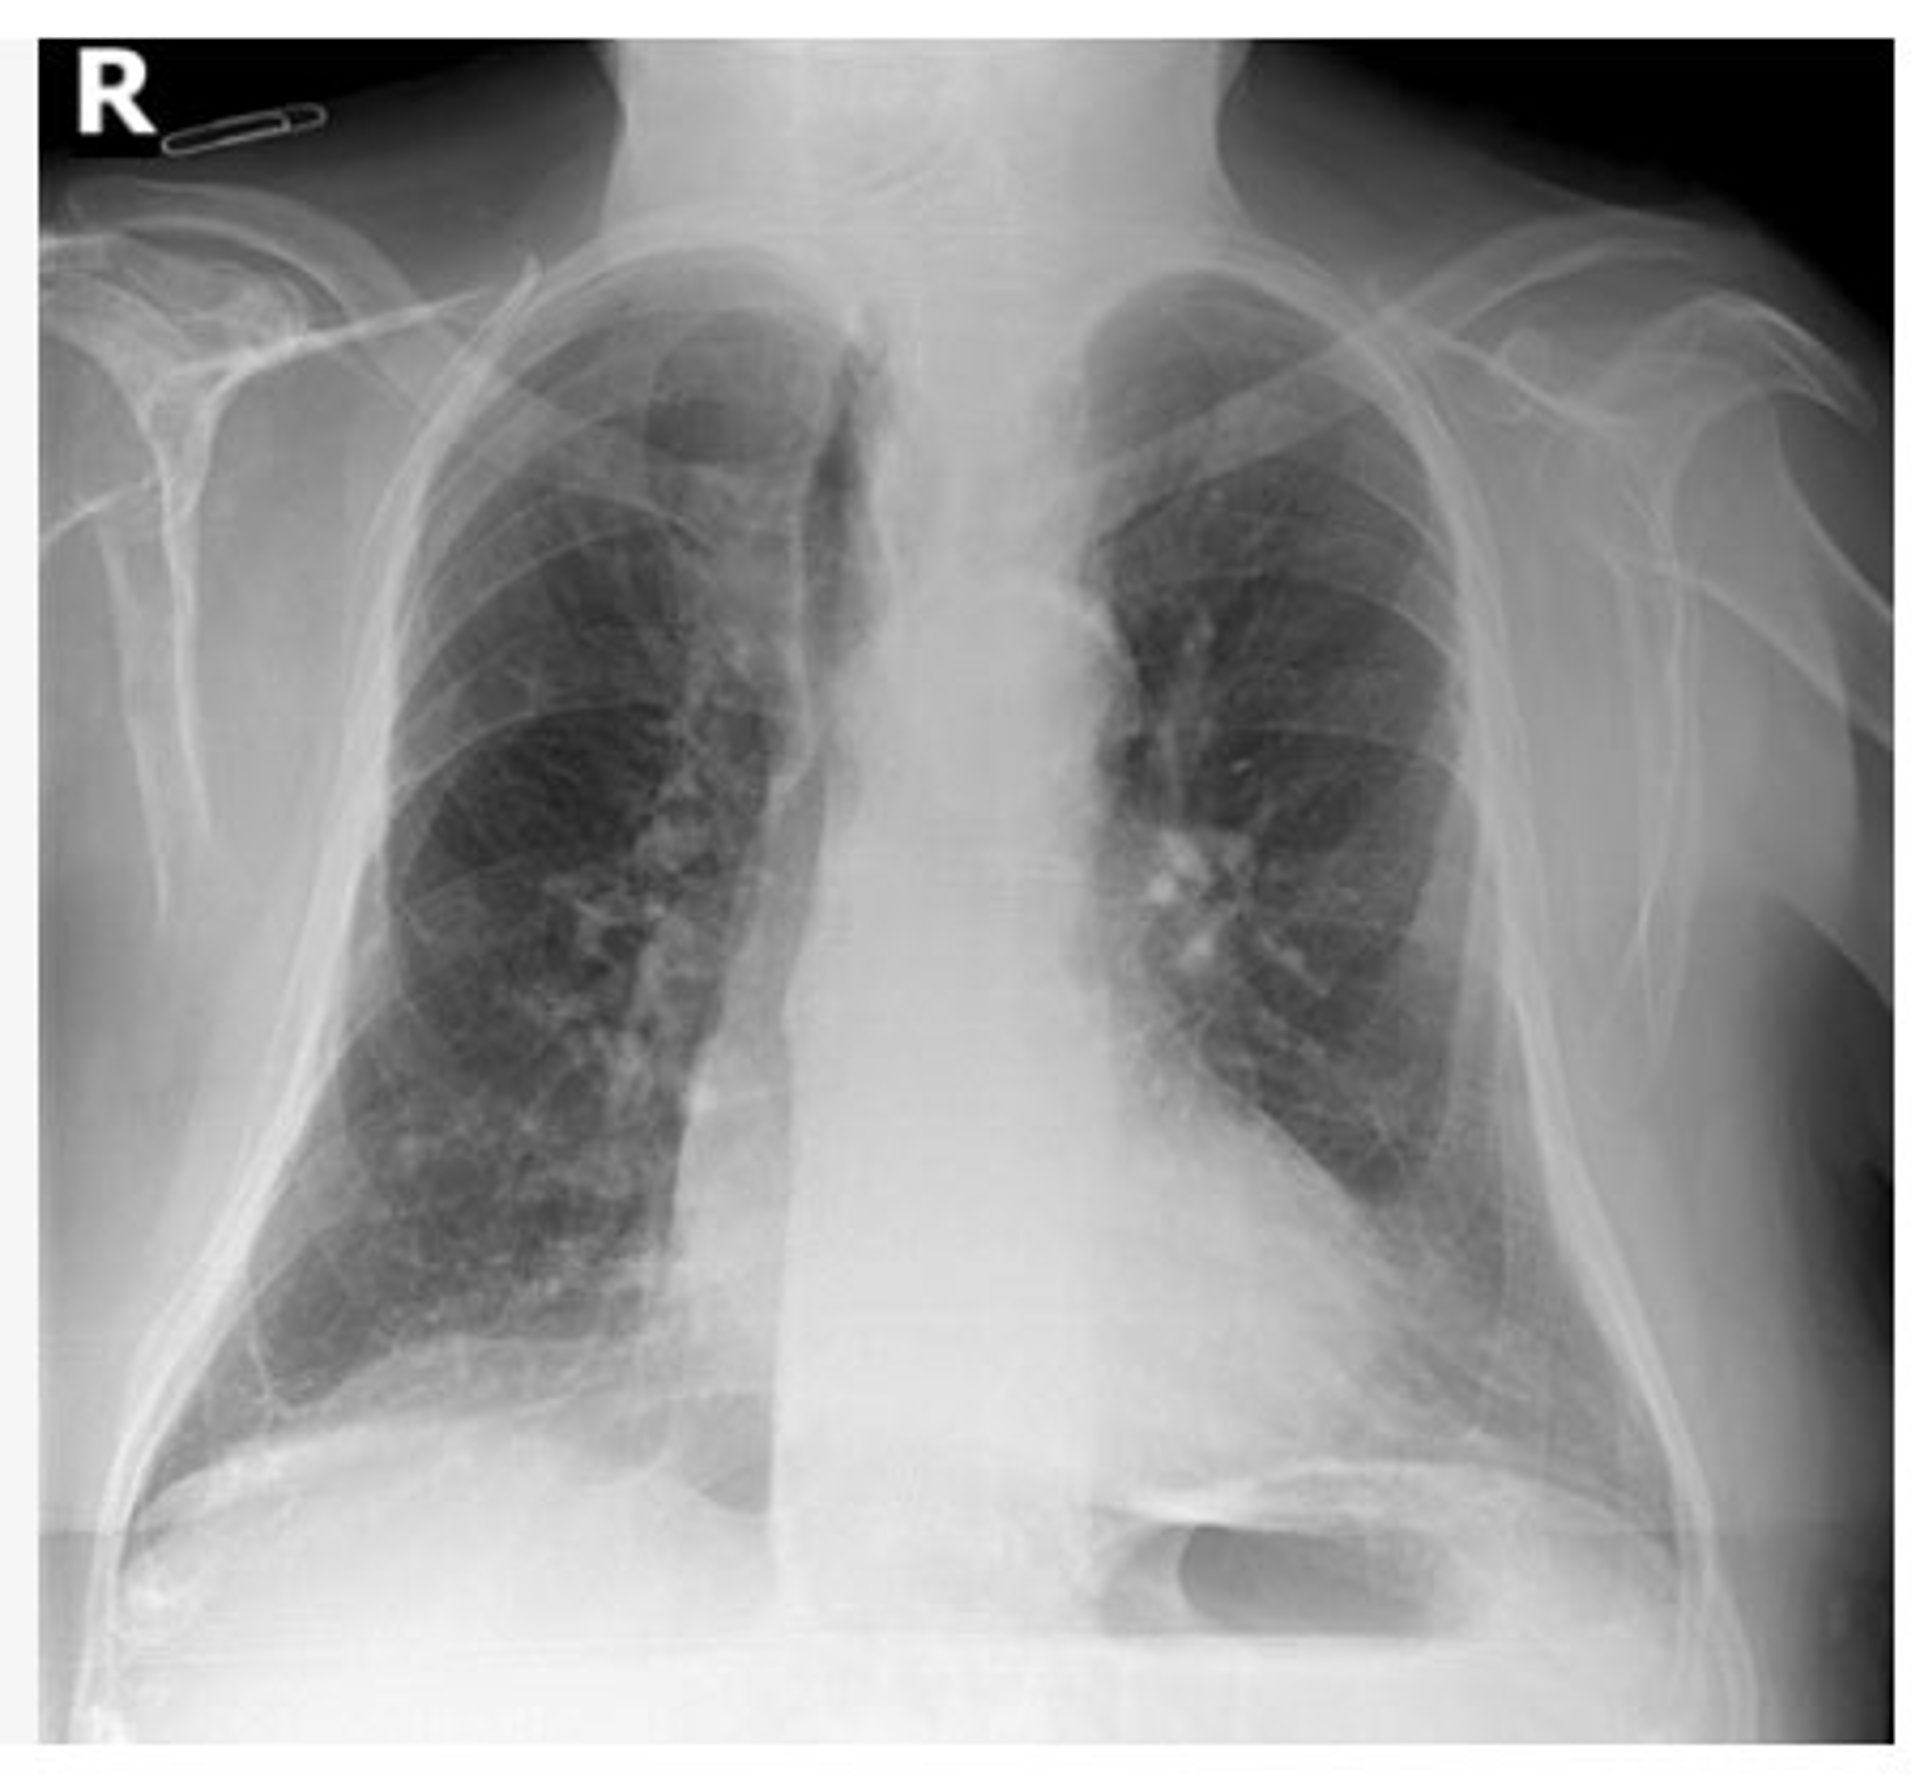

Archivo - Radiografía de tórax

Archivo - Radiografía de tórax - GVA - Archivo

Las tomografías computarizadas (TC) ofrecen un enfoque adicional para demostrar la eficacia de las diferentes vacunas contra el Covid-19 para reducir el impacto de un diagnóstico, según un estudio realizado por investigadores italianos y publicado en el 'American Journal of Roentgenology' (AJR) que ha analizado la evaluación de los hallazgos de la TC de tórax en neumonía en estos pacientes en la pandemia.

"La frecuencia y la gravedad de la neumonía fueron menores en pacientes con vacunación completa con ARNm y vacunas de vector de adenovirus que experimentaron infecciones de avance, en comparación con pacientes no vacunados", ha señalado el autor correspondiente Davide Bellini del departamento de ciencias radiológicas, oncología y patología anatómica en la Universidad de Roma La Sapienza de Roma (Italia).

La frecuencia de ausencia de neumonía fue del 15 por ciento en pacientes no vacunados, frente al 51 por ciento y el 29 por ciento en pacientes completamente vacunados con las vacunas BNT162b2 y ChAdOx1-S, respectivamente. Además, el CT-SS medio fue significativamente mayor en los pacientes no vacunados (9,7) que en los pacientes completamente vacunados con las vacunas BNT162b2 (5,2) o ChAdOx1-S (6,2).

"La observación visual mediante imágenes radiológicas del efecto protector de la vacunación sobre la lesión pulmonar en pacientes con infecciones recurrentes proporciona evidencia adicional que respalda el beneficio clínico de la vacunación", reiteraron los autores de este artículo de 'AJR'.